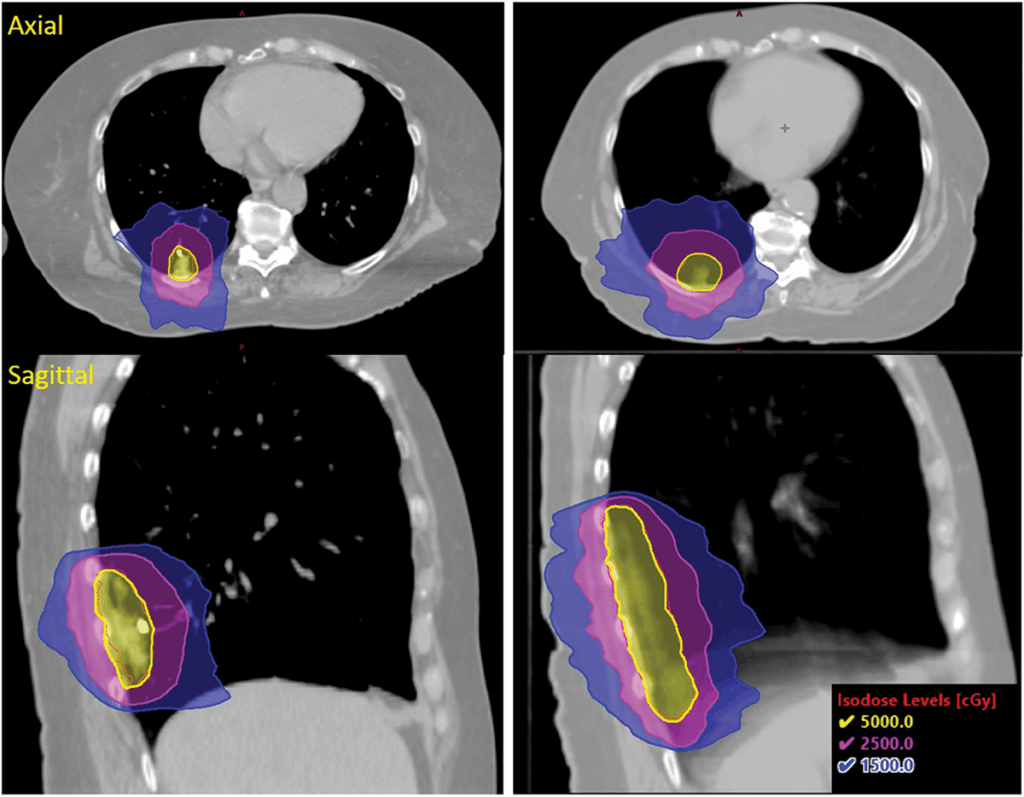

PTV Margin3 mm margin added to the GTV

Dose50 Gy in five fractions was prescribed to cover at least 95% of the PTV

• The CyberKnife® plan with Synchrony® real-time adaptive radiotherapy significantly reduced radiation dose to the OARs as shown in figures 3 and 5.